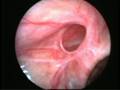

Can this operation done by laparoscopy?

Operation in hernia involves closing of the open passage through which the testis has come down. This can be done from outside as in open surgery or from inside by laparoscopy. If your child has got a hernia on one side, there is a 15 – 25 % chance that he / she may develop a hernia on the opposite side at a later date. With the help of laparoscopy we are able to look at the opposite side to see if the passage is open on that side as well. This can be closed at the same sitting if you wish to. Recovery from surgery, timing of surgery and discharge from hospital are the similar for open surgery and laparoscopic surgery.